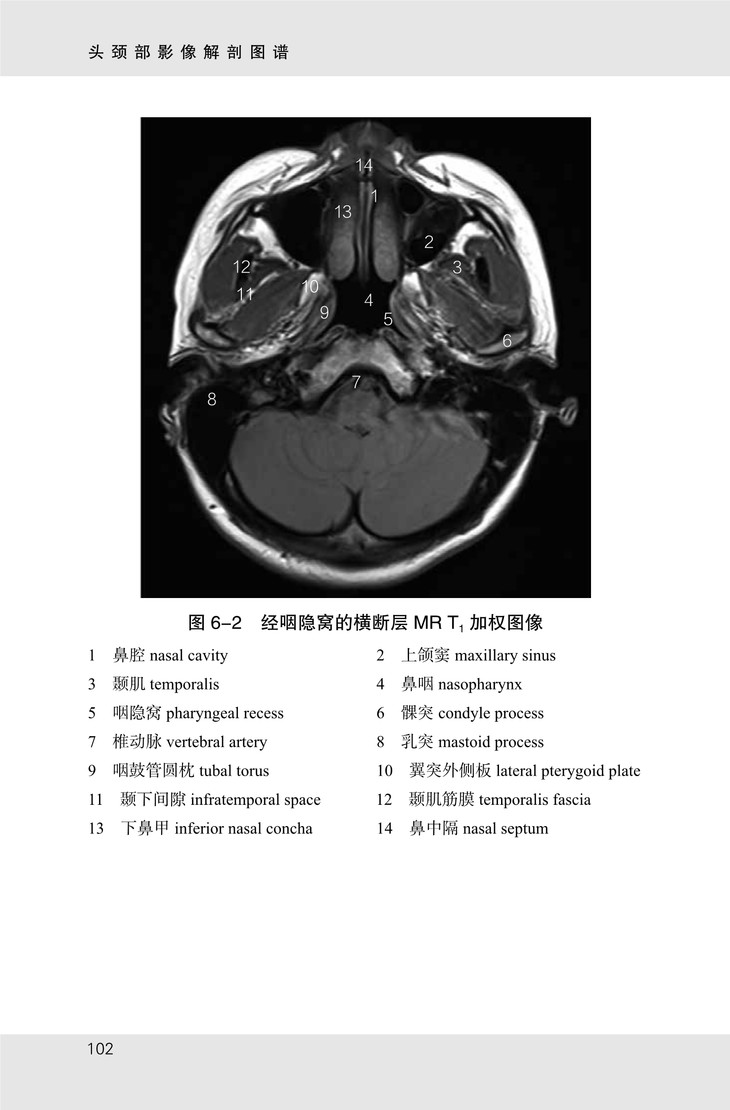

《头颈部影像解剖图谱》共包含眼眶、颞骨、鼻窦及喉部 CT 图像 107 幅,眼眶、内耳及颈部 MR 图像 70 幅。书中图像均来自山东省医学影像学研究所及济南市第三人民医院。MR 图像由 3.0T SIEMENS 磁共振扫描仪采集,序列包括 T1 加权像、T2 加权像;CT 图像由 SIEMENS 128层 CT 扫描仪采集,包括骨窗及软组织窗。

★ 内页插图 ★